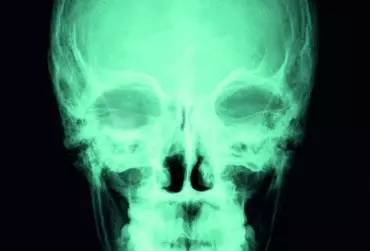

Rehabilitacja w urazach czaszkowo-mózgowych

Urazy czaszkowo-mózgowe to ogólne, aczkolwiek właściwe, kliniczne określenie różnych pod względem przyczyny i skutków urazów okolicy głowy. W krajach europejskich ok. 300 na 100 tys. osób rocznie jest hospitalizowanych z powodu urazu głowy. Urazy tego typu stanowią poważny problem medyczny, socjalny i ekonomiczny, a ich ogólna liczba wciąż wzrasta. Oczywiście większość urazów ma łagodny charakter i generalnie okazuje się niegroźna dla zdrowia poszkodowanego człowieka. Jednak ok. 25 na 100 tys. poszkodowanych osób wymaga hospitalizacji w wyniku umiarkowanego oraz poważnego uszkodzenia głowy, a statystycznie dziewięć z tych osób umiera w wyniku bezpośredniego, pierwotnego uszkodzenia mózgu lub w wyniku wtórnych zmian pourazowych mózgowia.